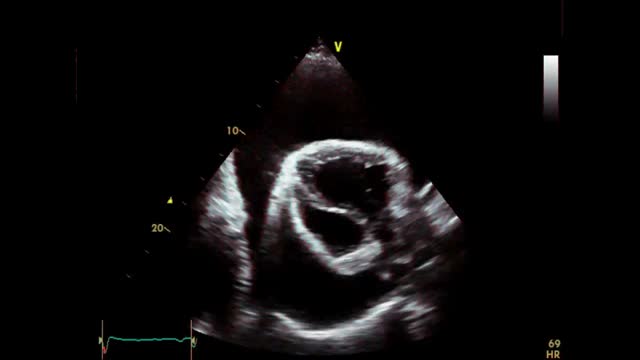

A 43-year-old man presented to the emergency department with a 2 week history of progressive breathlessness and fatigue. Physical examination revealed hypotension, tachycardia, jugular venous distension, pulsus paradoxus, and muffled heart sounds. His blood pressure was 90/60mm Hg, and the heart rate was 110 beats per minute. Chest x-ray showed a “water bottle configuration” suggestive of pericardial effusion (Fig. 1A). His electrocardiogram showed sinus tachycardia with small voltage QRS complexes and a degree of electrical alternans (Fig. 1B). Transthoracic echocardiography (TTE) revealed a large global pericardial effusion measuring>40mm in diameter with swinging of the heart freely in an anterior–posterior fashion (Fig. 1C, see video) and collapse of the right and left atria in end diastole, which was consistent with cardiac tamponade. Spectral Doppler demonstrated exaggerated respiratory variations of the mitral and tricuspid in-flow Doppler consistent with increased intrapericardial pressure and tamponade (Fig. 1D). A single axial, contrast-enhanced CT scan of the chest at the level of the heart showed a massive pericardial effusion (white arrows) surrounding the contrast-filled heart (LV=left ventricle) (Fig. 1E). The patient was immediately transferred to the coronary care unit where an emergency pericardiocentesis was performed which successfully drained 2.4 litres of serous pericardial fluid with immediate improvement of hemodynamics. Subsequent analysis showed a transudative pericardial fluid. All the connective tissue, cancer and infective markers were all negative and a diagnosis of idiopathic pericardial effusion was made. The patient was discharged well with resolution of the pericardial effusion on repeat TTE 4 days later. At 3 and 6 months follow-up, the patient was asymptomatic and well.